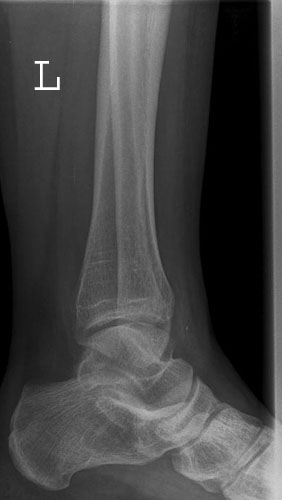

OSG a.p.

OSGapkeineRotation.jpg

Fehler

Leichte Außenrotation des Fußes. Die laterale Kante der distalen Tibia springt besonders markant vor und verdeckt teilweise den Schaft der Fibula.

Abhilfe

Fuß weiter nach innen drehen lassen, bis beide Malleolen auf einer Höhe parallel zum Film stehen.